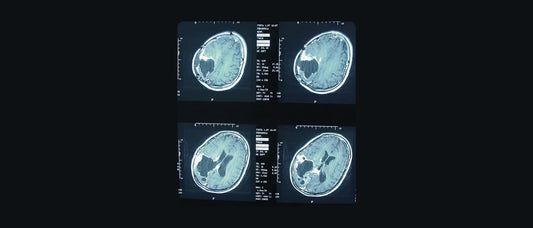

DefenderShield EMF Radiation Effect on Brain Cancer review of WHO study

cell phone radiation effect on brain activity

Study Shows Cell Phone Radiation Affects Brain ...

Preliminary research has shown that just 50 minutes of cell phone use is linked to an increase in brain activity in the area closest to the phone’s antenna according to a...